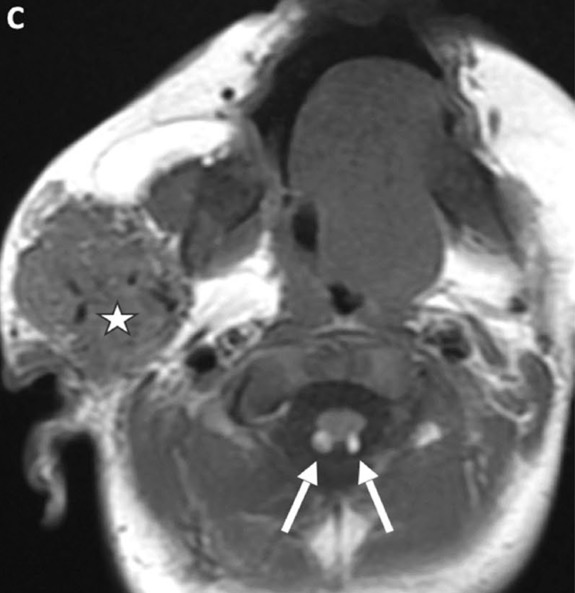

c. Lipomatose encéphalocraniocutanée (ECCL): peau, yeux, SNC)

ECCL: